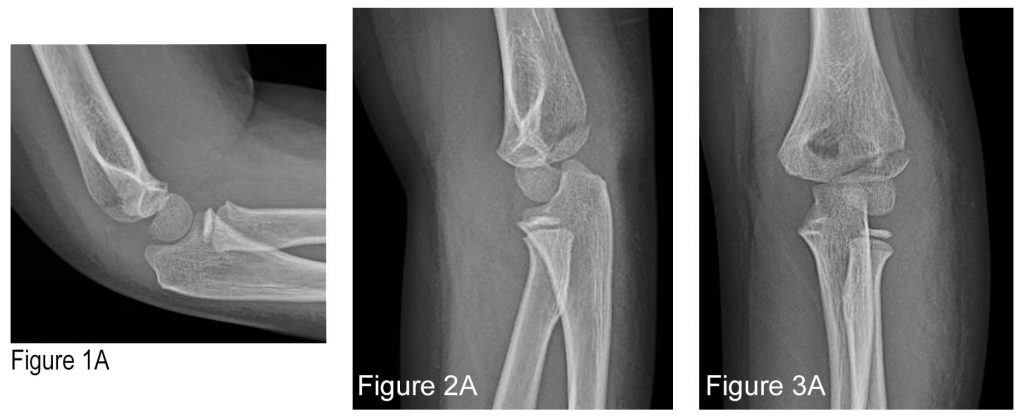

Figures 1A and 1B: Normal X-rays, 13-year-old male. 1) capitellum; 2) radial head; 3) internal (medial) epicondyle; 4) trochlea; 5) olecranon; and 6) external (lateral) epicondyle. Credit: Arun Sayal

Let’s run through it. The elbow has six ossification centers. CRITOE reminds us of their names and the specific order in which they ossify. Their clinical relevance rests on knowing the order and approximate ages in which they ossify, and therefore appear on X-ray (See Figures 1A and 1B).

In order of appearance, the six are:

C: Capitellum (lateral aspect of distal humerus)

R: Radial head (distal neighbor of capitellum)

I: Internal (or medial) epicondyle

T: Trochlea (distal neighbor of I, at medial aspect of distal humerus)

O: Olecranon (best seen on the lateral view)

E: External (or lateral) epicondyle

Because ossification always appears in this exact sequence, the presence of any single ossification center mandates the radiographic identification of those that precede it.